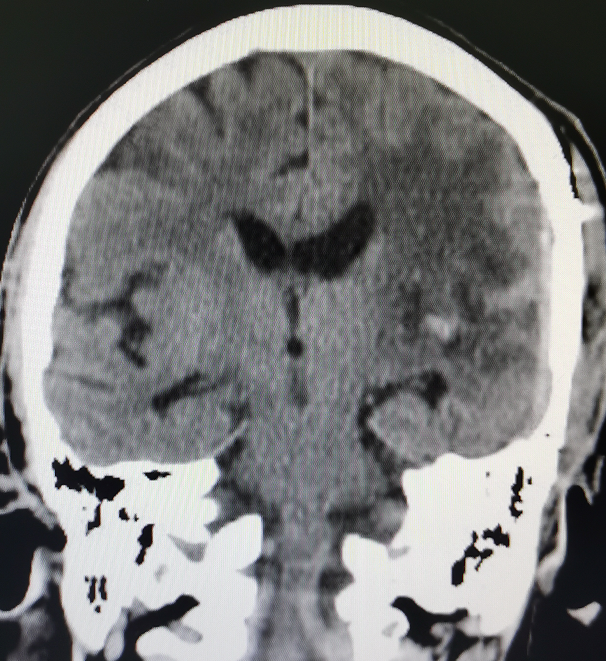

据术后复查颅脑CT(图3)结果显示,巨大的脑肿瘤已全部切除,瘤腔无渗血。术后患者意识、肢体功能、言语等情况均大幅度的好转,极大提高了病人的生活质量。

图3.术后影像资料,肿瘤被完全切除,脑室恢复,中线回位,脑水肿好转